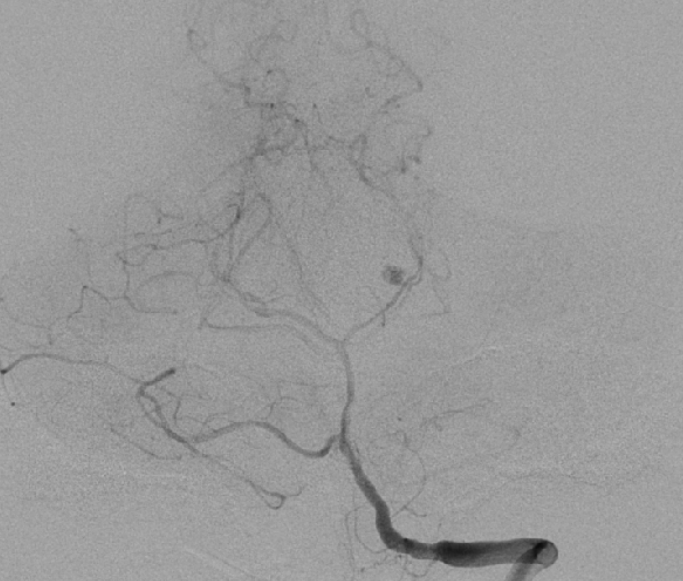

??术中造影见左侧大脑后动脉纤细

??术中微导管到位

??动脉瘤栓塞完全

??在多科室的密切合作下,周垂贤主任凭借精湛的手术技能,成功实施颅内动脉瘤介入栓塞手术,将动脉瘤完全栓塞,手术第一阶段顺利完成。手术第二阶段,经过术前严密规划,神经外科团队在机器人引导下实施脑立体定向血肿碎吸手术,机器人协助让手术效率大大提升,术中抽出血肿29毫升。整个手术在2小时内顺利完成。